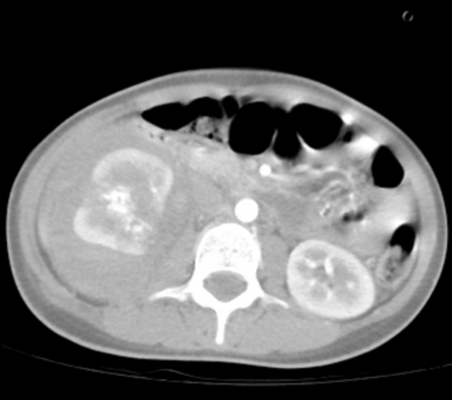

6月3日当天 , 广药大附二院(云浮市中医院)急诊接诊患者后 , 因其存在休克症状及体征 , 病情相当危重 , 立即开通绿色通道将患者收入ICU抢救治疗 。 入院诊断出其右肾损伤严重以及全身多处其他组织挫伤 , 如不及时救治 , 患者随时有生命危险 。

【郑祥|广州云浮两地联动,花季少女成功保肾】右肾破裂

经一系列救治 , 患者暂时病情稳定 , 尿液变清 , 考虑有保肾的希望 , 附二院医疗团队给予其保守治疗 。 就在大家长舒一口气的时候 , 第四天半夜 , 患者留置尿管中突然引出较多血液 , 如不及时治疗 , 患者随时可能出现大出血 , 危及生命 。 附二院泌尿外科主任邢钢第一时间请求附一院泌尿外科主任郑祥光协助治疗 , 郑祥光连夜对患者进行了远程会诊 , 经过诊治患者尿液逐步转清 。 为尽可能给患者保肾治疗 , 避免肾切除 , 两院泌尿外科团队决定将患者由附二院转至附一院进行进一步治疗 。